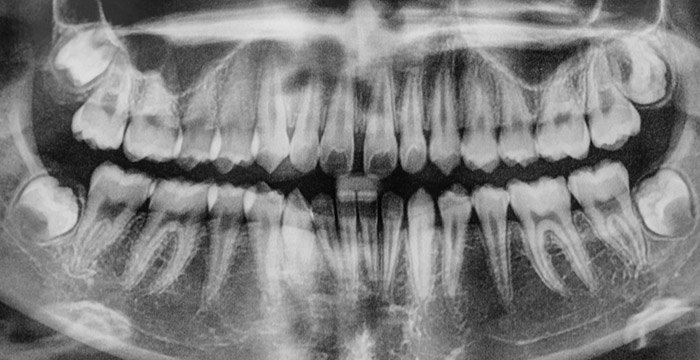

Рентгенологические исследования. Диагноз периодонтита можно подтвердить только при проведении рентгенологического исследования. Выбор рентгеновских снимков, необходимых для диагностики периодонтита, производится после клинического осмотра.

В самых простых случаях необходимы только два снимка (так называемые изображения «прикус-крыло»), но в более обширных случаях может потребоваться до 14 дополнительных рентгеновских снимков и/или панорамный рентгеновский снимок всего рта. Эти рентгеновские снимки показывают челюстную кость, окружающую зуб, и позволяют оценить тяжесть потери костной массы. На каждом рентгеновском снимке, сделанном в стоматологической практике, зубы должны проверяться на наличие кариеса и периодонтита.